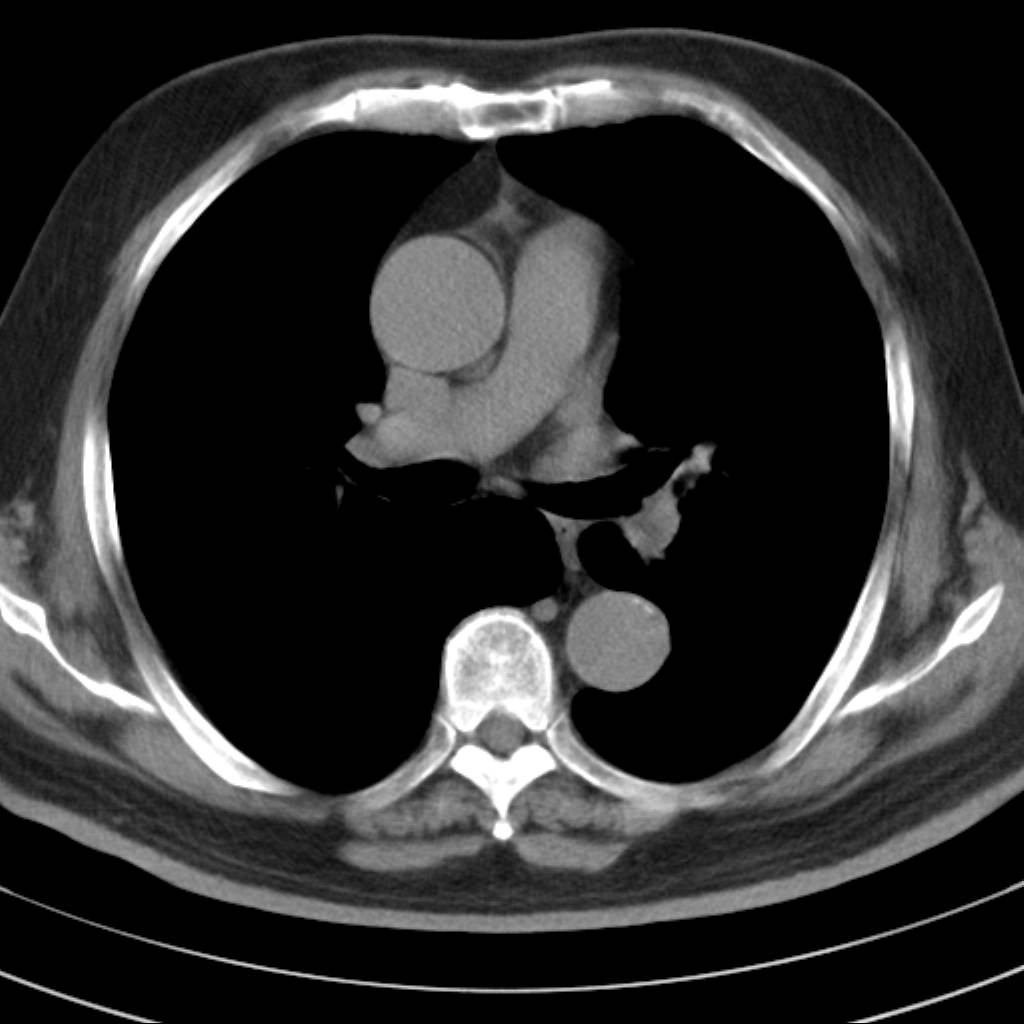

标题: CT18644:男,82岁,体检发现左肺阴影. [打印本页]

标题: CT18644:男,82岁,体检发现左肺阴影.

岁数太大,没有增强。麻烦见过的,给个诊断,顺便再说说病因

左侧中心型肺癌并粘液栓形成。很典型的。手套征。

支持 左肺上叶中央型肺癌并支气管内粘液栓形成。

支持考支气管扩张伴粘液栓,但导致粘粘液栓的病因有待进一步检查。支持左上叶支气管基部肿物,肺癌可能性大,但肿块似与肺动脉右支保持良好的伙伴关系,不除外为肺动脉扩张所致,建议增强。

左肺动静脉畸形,肺动静脉畸形(pavms)是肺血管发育异常,是肺动脉与肺静脉直接相通形成短路,通常包括一条供血动脉及一条或数条引流静脉,以及他们之间的异常血管团。约70%的患者伴发遗传性出血性毛细血管扩张症。 影像检查的目的在于确定病灶位置、大小、形态、数目。x线可表现为:1.结节型(直径小于3cm)2.团块型(直径大于3cm)3.弥漫型(肺内散在逗点状影),以团块状居多。 ct扫描可见单发或多发肺内结节,有的有蜿蜒迂曲的团块影,边缘光滑、锐利,增强ct扫描可见增粗、扭曲的血管影和/或类圆形的增粗的血管断面,甚至供血动脉及引流静脉。

平扫似avm,建议增强扫描。

病人已经去做mr了  等待结果中  有消息 我会进一步将结果发在网上